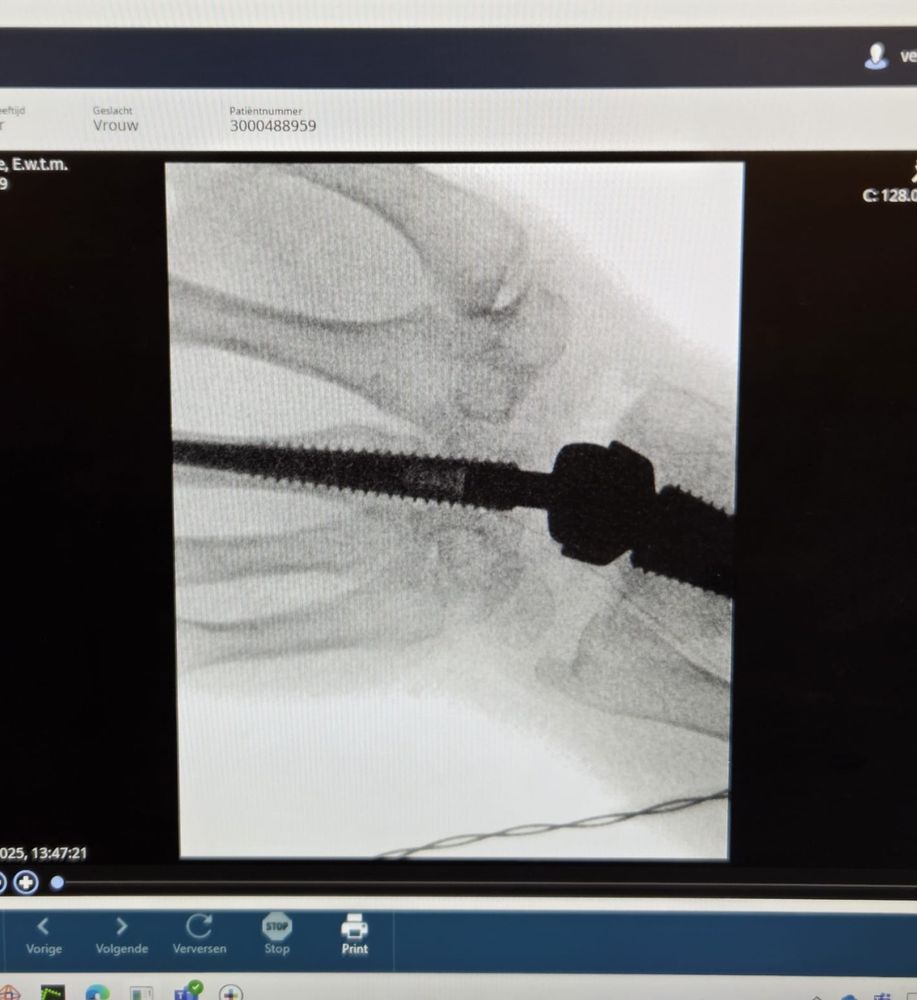

Ik heb een polsprothese gekregen 6 wkn geleden.